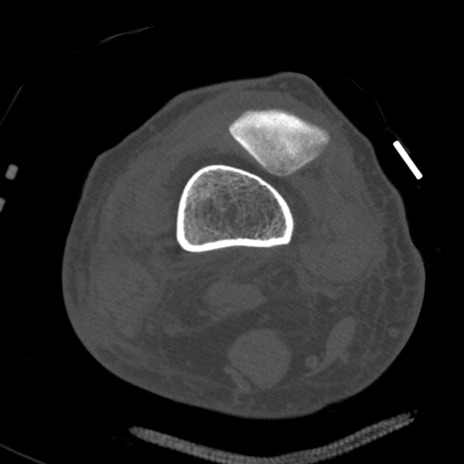

症例28 右膝関節CT(横断像)

右膝関節CT